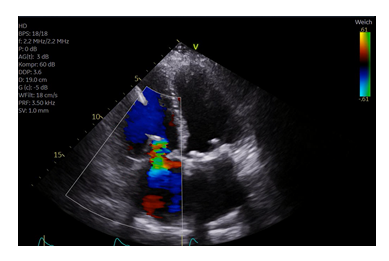

The patient was 71-year-old woman with a history of severe mitral and tricuspid regurgitation. 8 years prior, she had undergone mitral valve replacement (Perimount Magna Ease 29 mm) and tricuspid valve prosthetic annuloplasty ring (Edwards MC3-ring 32 mm). The patient complained of worsening right heart failure symptoms, with severe peripheral edema, and shortness of breath (New York Heart Association (NYHA) Functional Class III-IV). The was hospitalized several times for intravenous diuretic therapy due to right sided heart failure in the past year. Upon admission, physical examination revealed peripheral edema, jugular venous distension, and irregular heartbeat. The electrocardiogram showed atrial fibrillation. Echocardiography demonstrated normal left ventricular function. The mitral valve did not show significant abnormalities. A massive tricuspid regurgitation Grad V was documented (vena contracta width of 11 mm) (Figure 1A). The patient was evaluated by the Heart Team as to be at high risk for re-surgery of the tricuspid valve. TEER was performed by using the TriClip® device (Abbott, Vascular GmbH). During the TEER procedure, it was difficult to visualize the tricuspid leaflets in transesophageal echocardiography (TEE) due to shadowing from the prosthetic annuloplasty ring (Figure 2). This was resolved by utilizing transgastric visualisation (Figure 2) during deployment of the TriClip®. The right ventricular lead was visualized by X ray and echocardiography during the procedure (Figure 3). The device was implanted posterior to the RV lead which was in a central and anterior position into the tricuspid valve. TR was reduced to a Grad II (Figure 1B). Hemodynamic improvement was documented intraoperatively by an increase in arterial pressure up to 15 mmHg immediately after deployment of the Clip. Transvalvular gradient was 1,5 mmHg at the end of the procedure. Pacemaker interrogation did not show alteration of RV sensing or pacing.